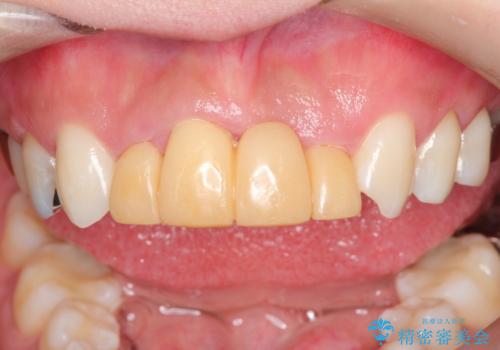

- 数年前に他医院で抜歯したままで過ごし、今回歯を入れたいとのことで来院された患者様です。

治療回数を短くしたいと1DAYインプラントを希望されました。

インプラント埋入手術は1回で全て行い、2ヶ月後にはセラミック治療で、審美回復と機能回復をしました。

来院回数が少なく、しっかり食事もできるとの事で非常に喜んで頂けました。